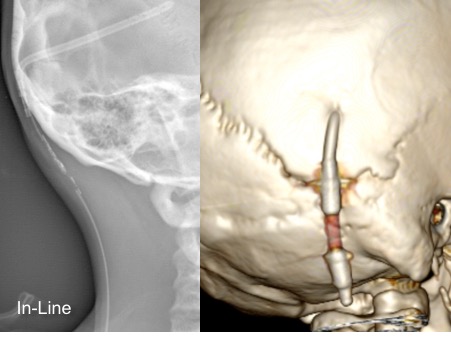

il existe un grand nombre de valves ; il n’est pas toujours aisé de les reconnaitre radiologiquement. voici la liste des plus courantes :

comment reconnaitre radiologiquement le type de valve ?